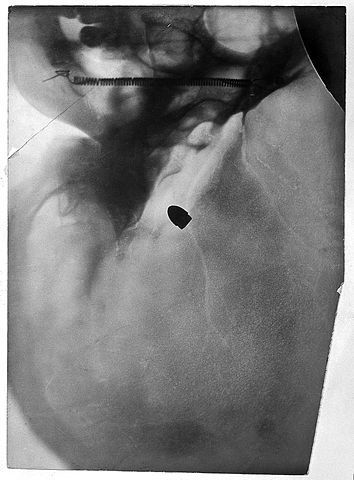

Not having been shot by a gun (thankfully), I’m a little naive in the department of gunshot injuries. However, a Facebook conversation the other day brought up the topic of characters treating gunshot wounds. Books, movies and TV shows will often depict a character “digging out the bullet” before wrapping up the wound.

This makes for great thematics, but I always doubted the practicality of digging out the bullet first. It turns out I’m right (self-high five), according to one of my favorite sources for ditch medicine, the Living Ready Pocket Manual: First Aid (disclaimer: we publish this at my work, and you should go buy it right now).

The author, Dr. James Hubbard, MD, recommends forgetting about the bullet until the wounded person (or character, in this case) can get to a hospital for proper assessment and treatment. Instead, focus on stopping the bleeding (apply pressure/coagulant), treating the wounded for shock (keep warm with blankets) and monitoring symptoms for relaying to a real doctor.

Hubbard has this to say about “digging out the bullet” ahead of real medical treatment:

In most circumstances, you don’t want to remove an implanted bullet. It’s almost impossible to find, and it may actually be corking up a big blood vessel.

Thousands of military members live with shrapnel in their bodies every day. Unless there’s initial infection from the wound itself, the body adapts to most metal without much serious problem.

The exact thing happened to Dick Moonlight, novelist Vincent Zandri's PI character. A shard of bullet left over from a botched suicide attempt remained in the titular character's head, causing him to black out at inconvenient moments. It's suggested the doctors can't remove the shard without killing him. Moonlight may be a work of fiction, but that's pretty close to reality.